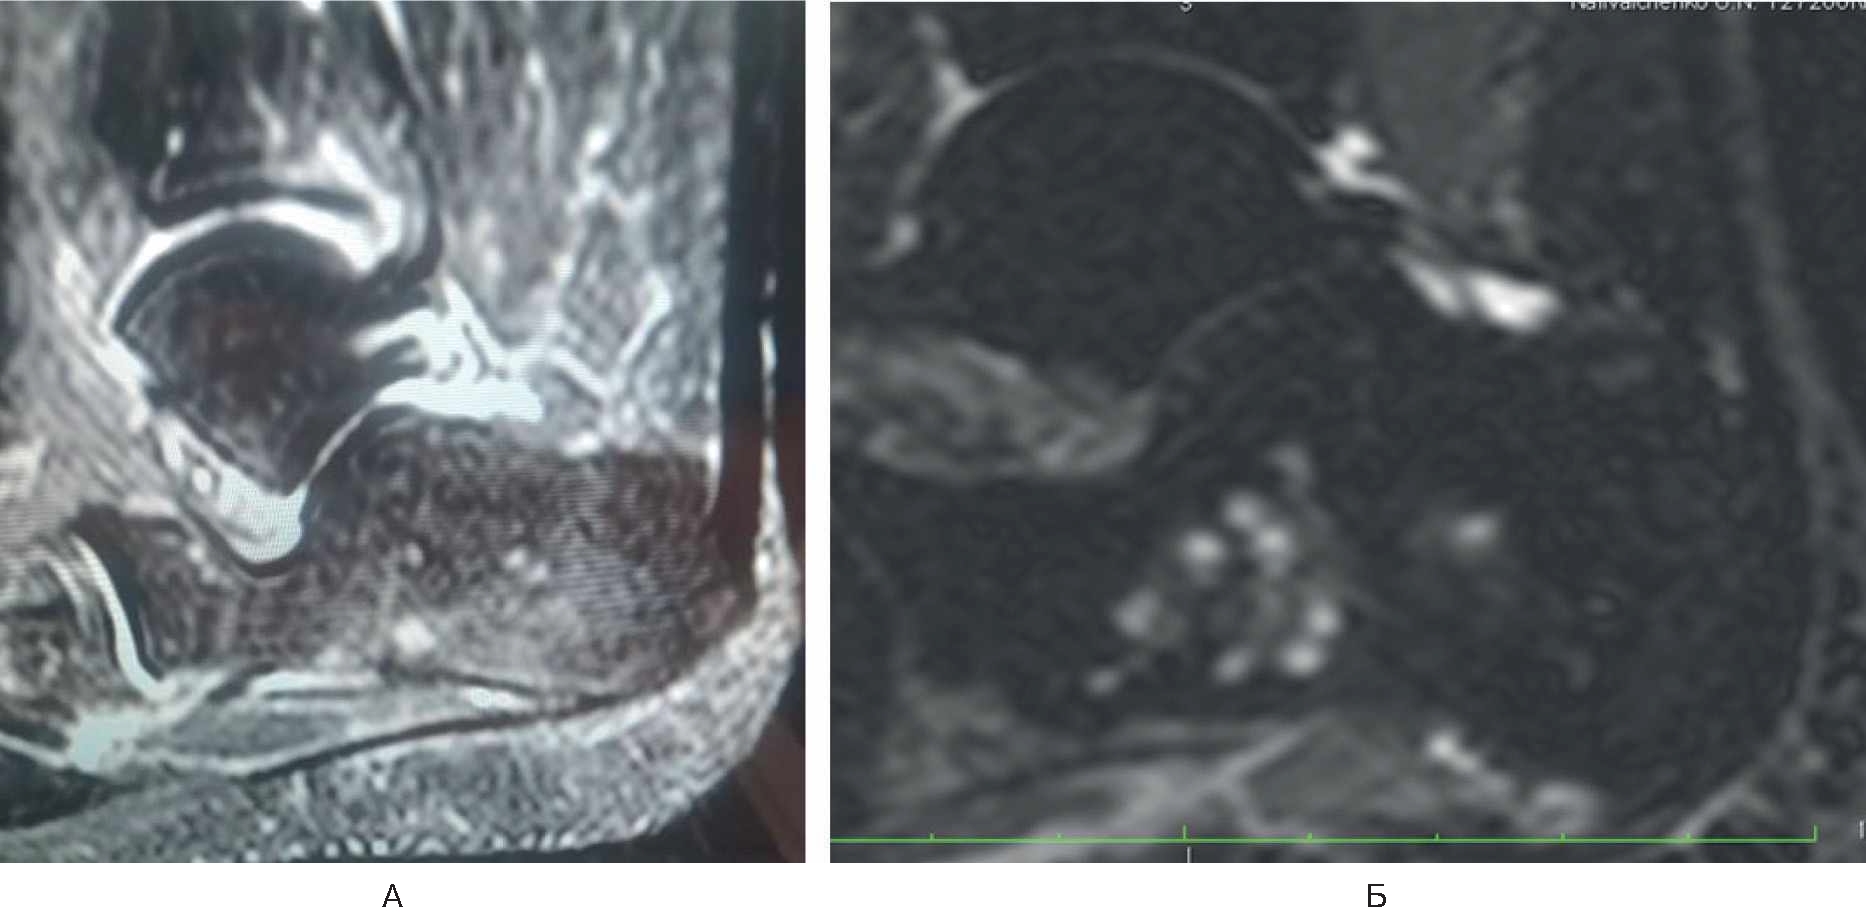

Спустя 6 мес стала отмечать боль (8 баллов по ВАШ) в области нижнего полюса надколенника в покое и при нагрузке, резкую боль – в нижнем полюсе надколенника при активном и пассивном сгибании в коленном суставе. Обратилась в травматолого-ортопедическое отделение. Семейный и соматический анамнез не отягощен. В феврале 2022 г. провели МРТ коленного сустава, обнаружен асептический некроз нижнего полюса надколенника (рис. 2). Выполнена артроскопия коленного сустава с декомпрессией очага некроза.

Рис. 2. МРТ коленного сустава у пациентки Б. Диагноз – асептический некроз нижнего полюса надколенника.

В раннем послеоперационном периоде пациентка отмечала снижение боли (интенсивность – 3 балла по ВАШ). Назначены терипаратид подкожно 20 мкг 1 раз в сутки в течение 2 мес и ношение ортеза на коленный сустав. На контрольный осмотр не явилась.